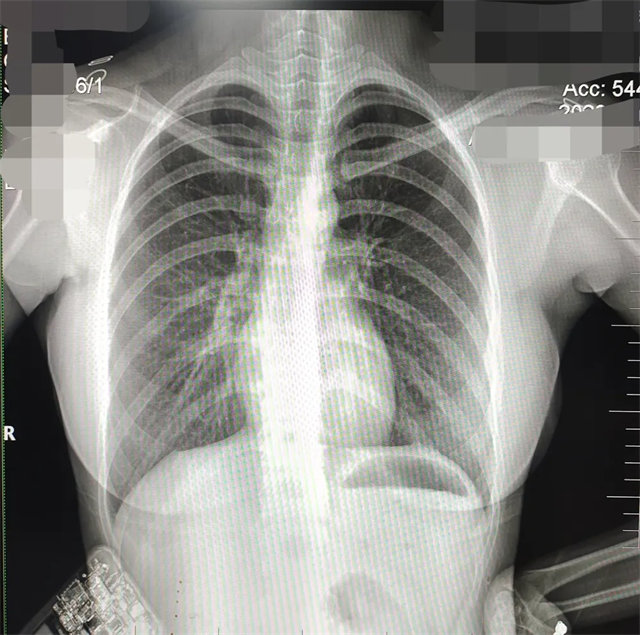

缺陷:雙側(cè)胸鎖關(guān)節(jié)不對稱,且有手機(jī)顯影。

解決:去除手機(jī)后,使患者左側(cè)緊貼成像件曝光。